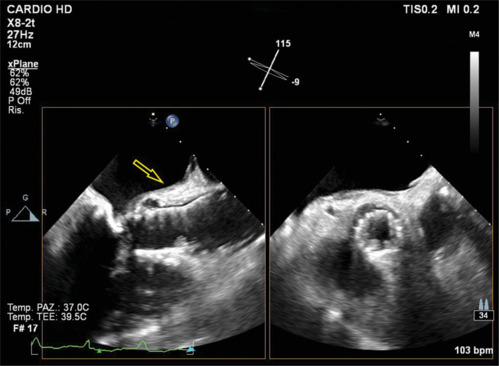

Abstract Image